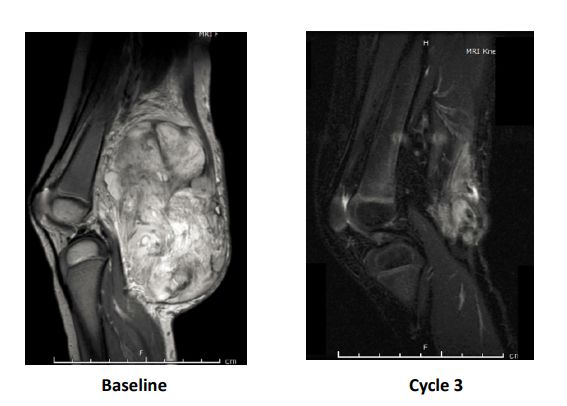

婴儿纤维肉瘤:一个年仅2岁的小女孩腿上长了个巨大的婴儿纤维肉瘤,化疗无效只能选择截肢。幸运的是她的肿瘤适合用LOXO-101,治疗3个周期后,肿瘤几乎完全消失。手术取出残余肿瘤后小女孩的腿保住了!